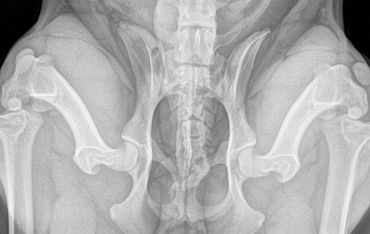

This technique requires 3 xrays views be taken while the dog is sedated.

The three views are

Often the distraction view shows greater laxity (looseness) in the hip than the hip extended view. This is because the hip extended view often masks hip laxity due to the position the socket is stretched into. This is why both views are required to be assessed with PennHIP scoring. The compression view allows the radiologist to assess the fit of the femoral head (ball) into the acetabulum (socket).